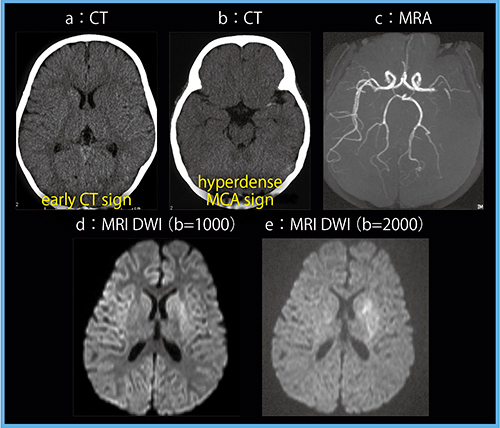

症例4は,4歳,女児,急性期脳梗塞症例で,心疾患の既往がある。昼寝からの起床時に上下肢麻痺が認められ,約3時間後のCTにてearly CT signが認められた(図7 a,b)。早期虚血の診断は小児も成人と同様に行うが,皮質と白質のコントラストが明瞭な画像が求められる。直後のMRI(1.5T)の拡散強調画像では,b値2000s/mm2(図7 e)にて病変が描出されているが,b値1000s/mm2(図7 d)ではわかりにくい。これとCT画像を比較すると,本症例ではCTの方が私には所見がわかりやすく,やはり適切な条件のCTは,小児においても強力な診断手法であると言える。

図7 症例4:急性期脳梗塞症例(4歳,女児)